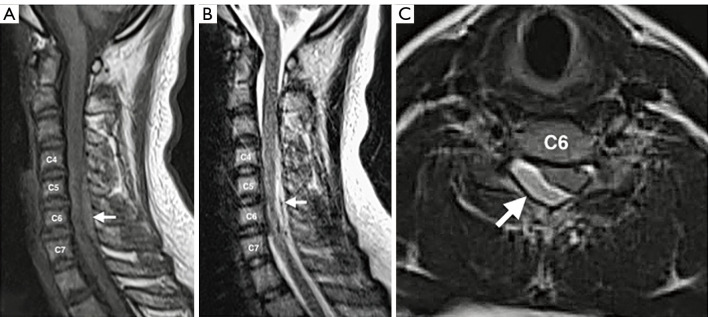

背景:自发性脊髓硬膜外血肿(SSEH)是脊髓硬膜外腔内的血肿,其根本原因不是外伤或先天性的,被认为是一种非常罕见的儿童神经外科急诊疾病,可导致脊髓压迫和神经功能障碍。本文就儿童 SSEH 的具体特征、临床表现和处理策略为临床医生提供有用的信息和指导,以获得更好的治疗效果:一名 14 岁男孩因颈部疼痛急性发作并向右肩放射,同时伴有进行性右侧偏瘫。颈椎磁共振成像(MRI)显示,C4-C7 处存在右侧后外侧急性脊髓硬膜外血肿。患者接受了紧急开门椎板成形术(C5-C6)和部分椎板切除术(C4 和 C7),并完全清除了血肿。术后患者完全康复,无神经功能障碍。我们在 PubMed 电子数据库中进行了文献检索,以找出 2000 年 1 月至 2023 年 12 月期间发表的以儿童 SSEH 为主题的英文文章。我们找到了81篇文章,共95例儿童SSEH病例,提供了性别、年龄、临床表现、病因、血肿位置、治疗方式和结果等方面的对比数据:儿童 SSEH 是一种非常罕见的神经外科急诊疾病。及时、正确的检查对确诊和早期手术减压至关重要。适当的手术减压可降低硬膜内压,增加脊髓的血液灌注,从而最终减少缺血,防止继发性脊髓损伤。因此,患者有望完全康复。

Case description: A 14-year-old boy presented with an acute onset of neck pain radiating to the right shoulder and progressive right hemiparesis. The cervical spine magnetic resonance imaging (MRI) revealed a right posterolateral hyperacute spinal epidural hematoma at C4-C7. The patient underwent an emergent open-door laminoplasty (C5-C6) with partial laminectomy (C4 and C7) and complete evacuation of the hematoma. The patient had a complete recovery after surgery with no neurological deficits. A literature search in the PubMed electronic database was performed to identify published English articles between January 2000 to December 2023 focusing on SSEH in children. We have found 81 articles with a total of 95 cases of SSEH in children, providing comparison data on sex, age, clinical presentation, etiology, location of the hematoma, treatment modalities, and outcomes.